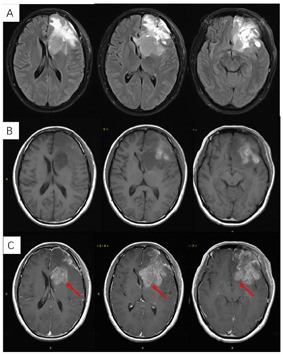

2018年3月、6月MR复查发现病灶范围逐渐增大(图6),提示不除外复发可能。患者除了轻微头痛之外并无明显不适,临床考虑假性进展,予安维汀100mg治疗后症状好转。2018年8月复查11C-MET PET/MR显像未见明显代谢增高病灶,证实为假性进展(图7)。2018年11月复查未见明显肿瘤复发,2019年3月2日MRI复查(图8)再次提示病变增大,考虑肿瘤进展。2019年3月行PD-1单抗(拓益)治疗,治疗过程中患者出现行走不稳,1月后患者不慎跌倒,外院就诊行颅脑CT未见明显出血。期间发现患者肝功能异常,给予护肝治疗后好转。2019年5月复查PET/MR(图9)提示左侧额叶前下部、左侧海马区及左侧颞叶前部蛋氨酸代谢较前次增高,其中左侧海马及左额叶直回ASL灌注相对增高,考虑复发可能,免疫治疗后存活。遂停用免疫治疗,根据患者全基因组测序结果选择靶向药物安罗替尼治疗(主要针对VEGFR、PDGFR、FGFR、c-KIT多个靶点),2019年12月复查PET/MR(图10)提示病变活性受抑。电话随访得知患者因武汉疫情影响无法按期治疗和复查,后合并肺部感染,于2020年8月去世。

本病例患者由低级别胶质瘤发展为高级别胶质瘤,结合分子分型诊断继发性胶质母细胞瘤。虽然手术后残留病灶较多,但经放化疗后效果显著。复发后尝试免疫治疗,效果不佳,后根据全基因组测序结果改用靶向治疗。整个治疗过程中依从性良好,规律复查,总生存期达3年余。回顾患者的诊治过程,可谓险象环生,几次MR复查都提示病变增大,在假性进展、复发后疗效评估和药物调整几个关键节点经PET/MR检查后得以拨云见日。